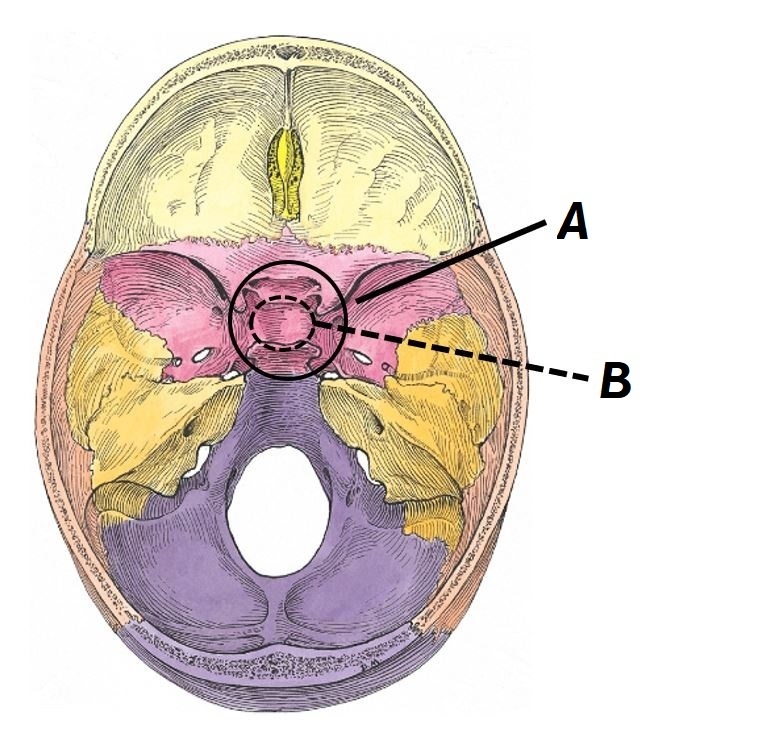

Name structures A and B

A - Optic chiasm

B - Pituitary gland